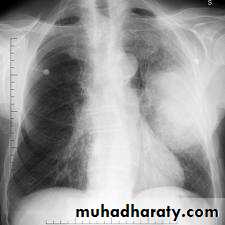

Secondary tumours of the lung

Blood-borne metastatic deposits in the lungs may be derived from many primary tumours, in particular the breast, kidney, uterus, ovary, testes and thyroid.

The secondary deposits are usually multiple and bilateral. Often there are no respiratory symptoms and the diagnosis is made on radiological examination(Cannon ball).

Cannon ball